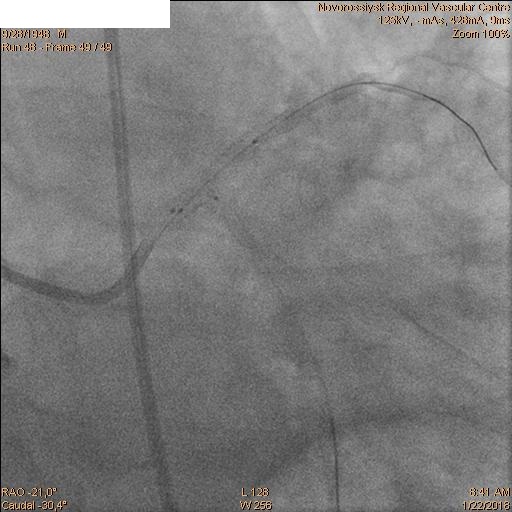

Последовательно заведены коронарные проводники в дистальные сегменты ПНА и ОА. Первым этапом была выполнена реканализация, баллонная ангиопластика ПНА баллоном 2.5х20 мм и стентирование ствола ЛКА с переходом на проксимальный сегмент ПНА стентом 4.0х28 мм.

Затем последовательно перепроведены коронарные проводники в дистальные сегмента ПНА и ОА. Баллоном 2.5х20 мм выполнена предилатация ячеек стента. Далее выполнено стентирование ствола ЛКА с переходом на проксимальный сегмент ОА стентом 4.0х28 мм. Затем баллонами 2.5х20 мм и 2.5х15 мм выполнена «kissing» дилатация ствола ЛКА, устья ПНА и устья ОА с великолепным ангиографическим результатом.